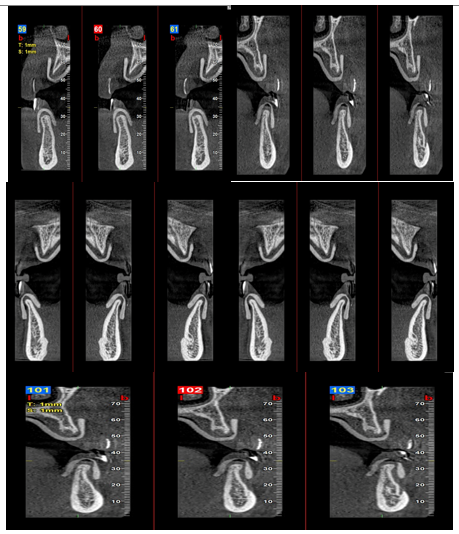

Radiographic and Digital Planning

Digital imaging played a central role in guiding the treatment protocol. Cone-Beam Computed Tomography (CBCT) was used to evaluate:

• -  Residual ridge volume and bone quality

• -  Relationship of anatomical landmarks (maxillary sinus, mandibular canal)

• -  Feasibility of parallel implant placement

Digital mock-ups and software-based planning ensured:

• -  Correct vertical dimension of occlusion (VDO)

• -  Ideal anterior-posterior tooth projection

• -  Harmonized smile line and lip support

This digitally guided approach helped predefine implant trajectories and prosthetic contours, minimizing intraoperative variability and supporting predictable esthetic outcomes.

Figure 2: Preoperative Panoramic Radiograph.